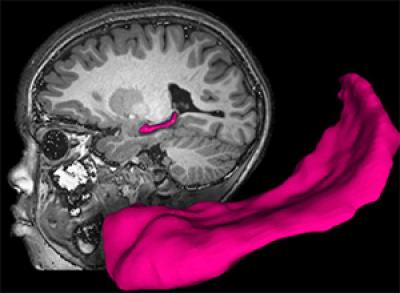

Using magnetic resonance imaging (MRI), the researchers found that poor children with parents who were not very nurturing were likely to have less gray and white matter in the brain. Gray matter is closely linked to intelligence, while white matter often is linked to the brain's ability to transmit signals between various cells and structures.

The MRI scans also revealed that two key brain structures were smaller in children who were living in poverty: the amygdala, a key structure in emotional health, and the hippocampus, an area of the brain that is critical to learning and memory.

Although the investigators found that poverty had a powerful impact on gray matter, white matter, hippocampal and amygdala volumes, they found that the main driver of changes among poor children in the volume of the hippocampus was not lack of money but the extent to which poor parents nurture their children. The hippocampus is a key brain region of interest in studying the risk for impairments.